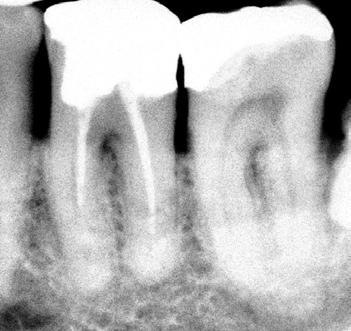

CASO CLÍNICO

Un paciente de 68 años, ASA I, pulso 64 bpm, PS 116 x 68 mmHb, SpO2 98%, temperatura 36,5 ° C, llegó al consultorio odontológico quejándose de dolor constante, de baja intensidad, y espontánea, en el área bucal y apical del diente 23 (Figura 1). Ella presentaba un edema intraoral, dolor durante la masticación y percusión vertical. Ella relató haber sido sometida a un tratamiento endodóntico en el diente 23 hace más de 35 años. En el examen radiográfico periapical, fue posible visualizar un tratamiento endodóntico ineficiente, con una obturación endodóntica con cono de plata y la presencia de periodontitis apical sintomática. Se ha diagnosticado un absceso apical agudo.

Figura 1- Radiografia inicial

El tratamiento propuesto fue el retratamiento endodóntico, porque en el tratamiento anteriormente realizado ocurrió una limpieza y ajuste inadecuado del canal, llevando a una obturación endodóntica con cavidades, manteniendo la infección intraconducto. Una microcirugía endodóntica fue contraindicada debido a la presencia de un tratamiento endodóntico anterior insuficiente.

El retratamiento endodóntico comenzó con el acceso a la cámara pulpar usando una Broca Dental Predator Turbo (Angelus - Londrina - Brasil). El cemento en torno al vástago del cono de plata fue removido con una punta ultrasónica E7D (Helse Ultrasonic-Brasil) (Figura 2). Después de la exposición de la parte coronaria del cono de plata, una E5 - Punta Cónica Larga Ultrasónica (Helse Ultrasonics - Brasil) fue usada para vibrar el cuerpo del cono de plata. Aunque la baja potencia ultrasónica ajustada en un 15%, ocurrió una separación (Figura 3). Debido a la falta de adaptación del material de la obturación en el tercio apical, parte del fragmento de cono de plata fue removida de la lesión periapical.

Figura 2 - Vista del conducto obturado de la parte coronaria del cono de plata

Figura 3 - Primera separación del cono de plata

El modelo del conducto radicular se realizó utilizando Lima Reciproc R25 (VDW - Alemania) seguido por Lima Reciproc Azul RB50 (VDWAlemania). Durante el retratamiento endodóntico, se realizó una irrigación abundante con un 2,5% de hipoclorito de sodio. Después de varios intentos para quitar la parte remanente del cono de plata, otra separación ocurrió (Figura 4). La parte del cono de plata fue removida del canal. Sin embargo, el otro fragmento no pudo ser eliminado.

Figura 4 - Expulsión del cono de plata

En esta fase del tratamiento, el control de desinfección adecuado no se había alcanzado. La presencia del fragmento, no permitía una desinfección apropiada del conducto radicular. Debido a esto, el dolor espontáneo, aunque disminuido, no cesó. Como resultado del fallo en el control adecuado de infección, una cirugía complementaria fue propuesta para remover el fragmento apical. Antes de entrar en la microcirugía, el conducto radicular estaba concluido.

El retratamiento endodóntico del conducto obturado fue realizado con un enjuague final con EDTA 17% pasivamente activado ultrasonicamente, seguido por obturación del conducto radicular usando conos de gutapercha con BIO-C® REPAIR (Angelus - Brasil). BIO-C® REPAIR es un nuevo Cemento Endodóntico Biocerámico Listo para Uso. Puede ser colocado de la jeringa directamente al conducto radicular. Los conos de gutapercha fueron compactados con una técnica de compactación fría vertical (Figura 5).

Figura 5 - Obturación endodóntica

ambientes húmedos, inducción y conducción en la formación de tejidos duros, cementogénesis con consecuente formación de adherencia periodontal normal, hacen el material más adecuado para estas situaciones clínicas. En este caso, se utilizaron nuevos materiales biocerámicos para obturación de la cavidad retrógrada. En primer lugar, el BIO-C® REPAIR (Angelus - Brasil) se utilizó para obturar el espacio en el conducto radicular. Un tapón apical de BIO-C® REPAIR (Angelus - Brasil) fue colocado sobre la raíz, sellando la retro cavidad (Figura 10, Figura 11).

El seguimiento de 6 meses mostró una cicatrización ósea muy rápida. Clínicamente, ya no tenía signos ni síntomas de una enfermedad endodóntica (Figura 12). La cicatrización ósea rápida puede estar relacionada con la liberación de calcio de este nuevo material de reparación biocerámica que contiene tungstato de calcio como radiopacificador en lugar de Óxido de Bismuto de su antecesor (MTA convencional). Además, el tamaño de las partículas biocerámicas son menores que del MTA, permitiendo más contacto con los tejidos circundantes, aumentando la respuesta biológica.